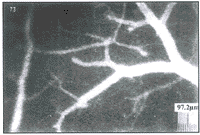

本实验采用了FITC标记的红细胞和RITC标记的右旋糖酐二种不同的荧光示踪物, 同时显示 红细胞流动和微血管几何形态, 从而可以明确的确定血管壁的位置, 而避免了通常方法难 以区别细胞流柱和血管壁内直径之间的误差。 同时用标记的红细胞来显示流速也大大提高 了血流速度测量的精确性。 图2和图3分别显示了用FITC标记的典型脑的微血流的图像和RIT C标记的微血管几何图像。 图4、 5分别显示了针刺组在针灸后和非针刺组放血后血流速度 、 血流量在30 min和60 min的改变。 从图中可以看出: 针刺组针刺前三里对大鼠脑微循 环的影响: 针刺30 min后的改善不大, 而在针刺后60 min血流速度(图4)及血流量(图5)均 有 增加, 但P值仍>0.05。 由于血PCO2的变化直接影响血流速度的改变。 PCO2 越高, 血流越快。 故此, 实验始终在血PCO2的严格监测之下。 实验显示, 在本实验 中二组动物的PCO2均保持在正常范围时, 测得针刺组60 min后血流速度较未放血时增加 39.07%±102.3%, 而非针刺组是未放血的-22.3%±39.07%, 处于降低状 态。 针刺组脑血流量增加为未放血时的62.6%±100.1%, 而非针刺组在60 min时 比未放血时降低为-10.7%±20.5%。 针刺组60 min后的传导指数与未放血时相比增 加163.3%±129.5%, 而非针刺组为37.1%±40.8%。

图2 用FITC标记的典型脑的微血流的图像

图3 标记RITC-Dextran后的微血管网络及血管直径